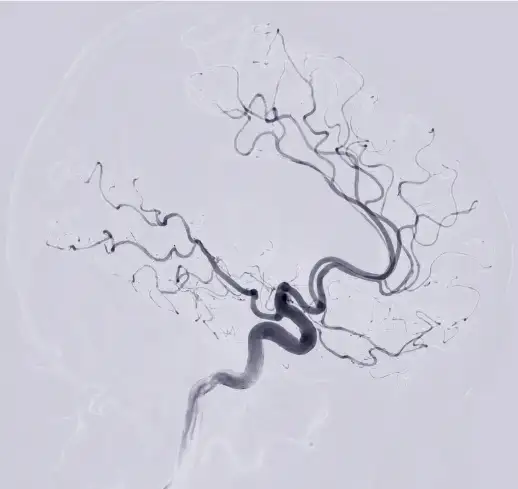

뇌경색 원인 2. 뇌동맥류

뇌동맥류는 뇌혈관이 약해져 부풀어 오른 것을 말합니다. 뇌동맥류가 터지면 뇌출혈이 발생할 수 있습니다.

뇌경색 치료방법 2 . 혈관내 혈전 제거술

혈전용해제 치료가 불가능한 경우에는 혈관을 직접 뚫어주는 수술 치료를 시행하기도 합니다. 혈관내 혈전 제거술은 카테터를 혈관에 삽입하여 혈전을 제거하는 방법입니다. 혈관내 혈전 제거술은 혈전용해제 치료보다 효과가 좋지만, 수술의 위험성도 있습니다.